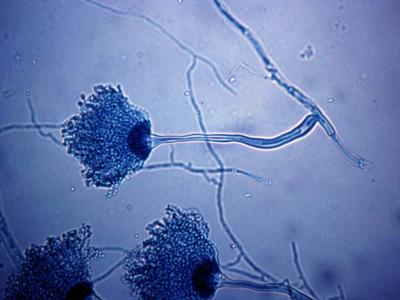

दिल्लीत नव्या फंगसमुळे होणाऱ्या मृत्यूंमुळे चिंतेत भर पडली आहे. एम्समध्ये दोन रुग्णांना एस्परजिलियस लेंटुलस नावाच्या फंगसची लागण झाली. या प्रकारच्या फंगसवर कोणत्याही औषधाचा परिणाम होत नाही.

क्रॉनिक ऑब्स्ट्रक्टिव पल्मोनरी डिजीजचा सामना करत असलेल्या दोन्ही रुग्णांचा उपचारादरम्यान मृत्यू झाला. एस्परजिलियस लेंटुलस फुफ्फुसावर परिणाम करतं. २००५ मध्ये वैद्यकीय जगताला या फंगसची औषध पटली. तेव्हापासून आतापर्यंत अनेक देशांमध्ये एस्परजिलियस लेंटुलसचे रुग्ण आढळून आले आहेत.

एका दशकापूर्वी २०० ते ३०० फंगसमुळेच माणूस आजारी पडायचा. मात्र आता या प्रजातींची संख्या ७०० च्या पुढे गेली असल्याचं डॉ. अरुणलोक चक्रवर्तींनी सांगितलं. ते जागतिक आरोग्य संघटनेच्या फंगस केंद्राचं नेतृत्त्व करतात. ७०० पैकी अनेक प्रजातींवर औषधांचा परिणाम होत नसल्याचं त्यांनी सांगितलं.

बुरशीमुळे होणाऱ्या आजारांना फंगल इन्फेक्शन म्हटलं जातं. बुरशी पर्यावरणात आढळून येते. बुरशीमुळे होणारे बरेचसे संसर्ग लगेच बरे होतात. मात्र काही संसर्ग अतिशय घातक ठरतात. त्यामध्ये कँडिडा किंवा एस्परजिलियस फंगसमुळे होणाऱ्या संसर्गाचा समावेश होतो.

फंगसमुळे होणाऱ्या संसर्गामुळे जगभरात दरवर्षी जवळपास १५ लाख लोकांचा मृत्यू होतो. रोगप्रतिकारशक्ती कमी असलेल्या, मधुमेह आणि किडनीच्या आजारांचा सामना करणाऱ्यांना फंगसचा धोका अधिक असतो.